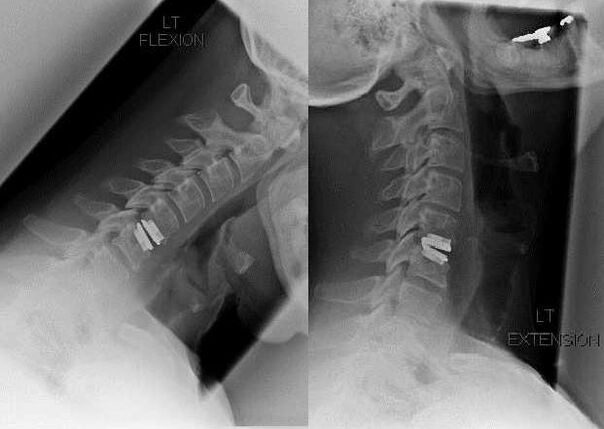

Indikácie pre chirurgickú intervenciu zahŕňajú neúčinnosť konzervatívnej liečby, ako aj komplikácie cervikálnej osteochondrózy, napríklad diskogénnu myelopatiu, syndróm vertebrálnej artérie a radikulárny syndróm. Na dekompresiu miechy, krvných ciev a miechových koreňov sa vykonávajú tieto operácie: